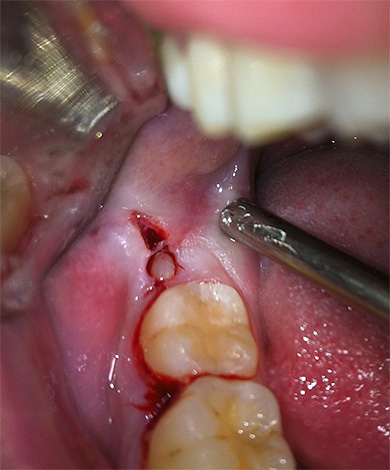

Foto dei denti del giudizio rimossi:

Nella foto - un dente del giudizio rimosso in alcune parti: